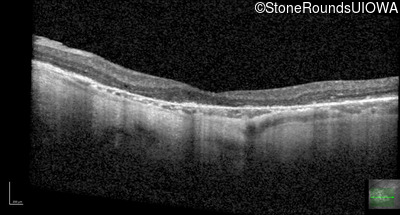

Optical Coherence Tomography - Left - 20/25 +3

Exemplar / OCT Stack